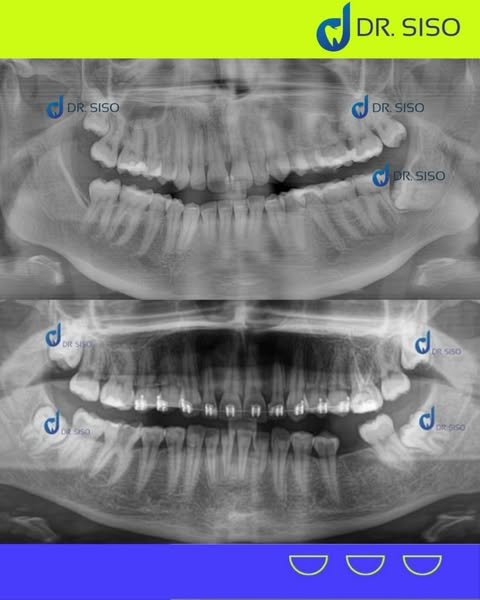

Sim, em muitos casos. Mesmo sem dor, o siso pode estar mal posicionado, pressionando outros dentes, causando reabsorção óssea ou prejudicando a mordida. A avaliação clínica e radiográfica é essencial para decidir com segurança.

Sim! É comum extrair até os quatro sisos em um único procedimento, especialmente quando o paciente quer otimizar a recuperação e evitar múltiplas cirurgias.